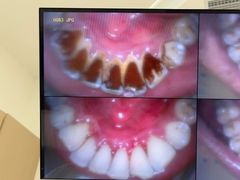

• 德伦口腔(海珠总院)

• -德伦口腔(海珠总院)